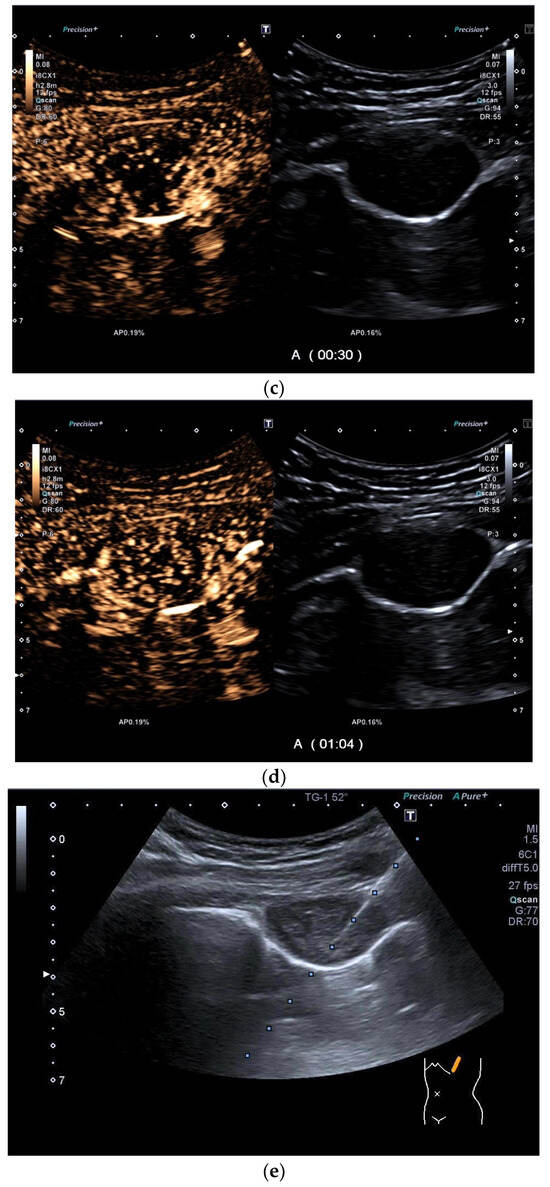

| Splenosis | Round, homogeneous lesions. Macrovessels on CDI are possible. Spleen-typical contrast behavior in CEUS with long-lasting contrast enhancement over several minutes. |

- Kroenig, J.; Zadeh, E.S.; Westhoff, C.C.; Klemmer, A.; Alhyari, A.; Görg, C. Diagnosis of Thoracic Splenosis by Contrast-Enhanced Ultrasound (CEUS). Ultraschall Med. 2022, 44, 645–646. [Google Scholar] [CrossRef]